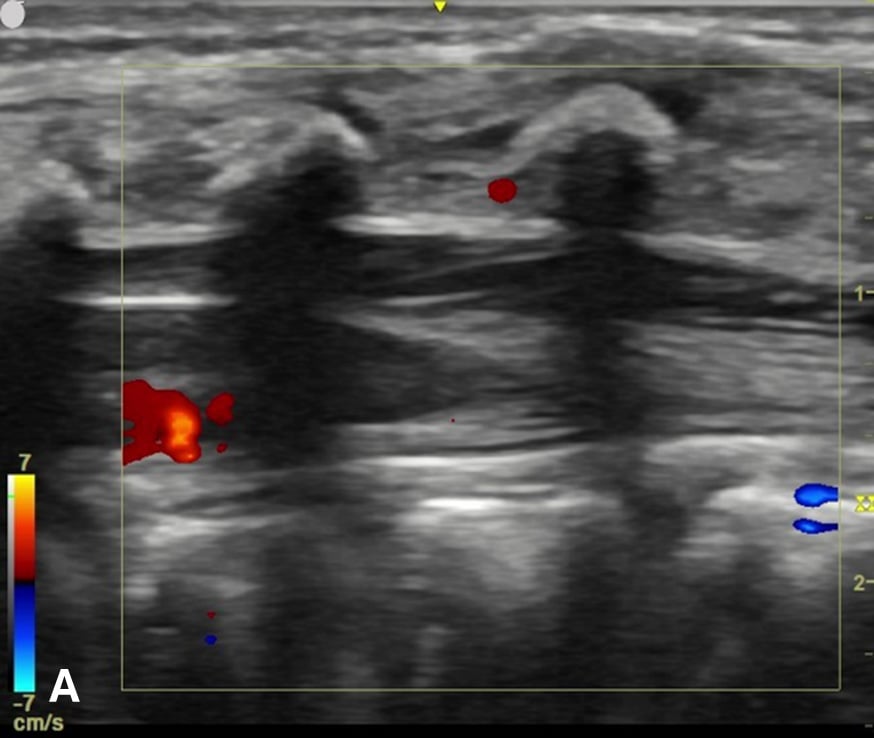

Figure 3 - Color Doppler US image of the spinal canal:

Figure 3A - The sagittal view demonstrates no prominent spinal vessels.